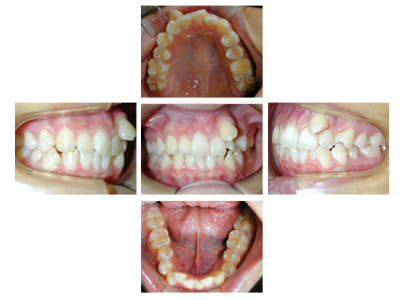

新舞子在住 I.Y様(15歳女性)

患者様は上下顎歯列弓の狭窄と上下顎前歯の叢生を主訴としてお母様とともに来院されました。

犬歯関係・臼歯関係は良好です。

![]() |

犬歯関係・臼歯関係は良好ですので、かみ合わせを崩さないように矯正治療をすすめます。

上下顎前歯の叢生を改善するために上下顎両側第1小臼歯を4歯抜歯して治療します。

0.14インチラウンドのニッケルチタンワイヤーで治療開始して0.16×0.16レクタンワイヤーで治療をすすめていき叢生を改善します。

できたスペースを利用して叢生の改善と臼歯のかみ合わせの改善を行います。

治療の前に叢生のためずれていた中切歯の正中は一致しています。犬歯関係、臼歯関係も1対2歯でよく咬んでいます。

口腔衛生状態が治療中に不良でした。

治療費用:60万円

動的治療期間:2年4か月